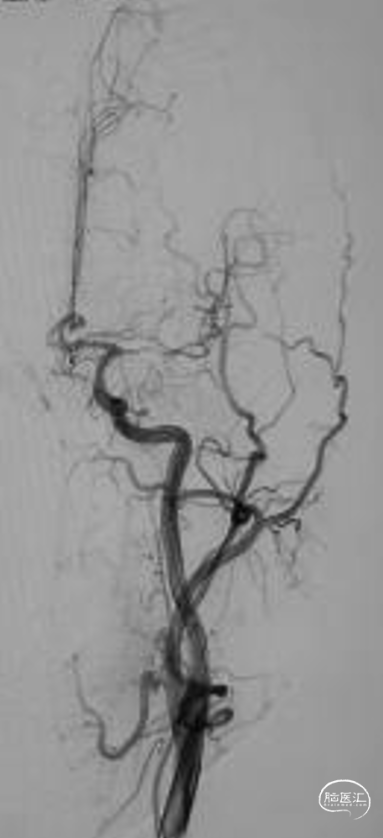

➢脑血管DSA

➢LCCA